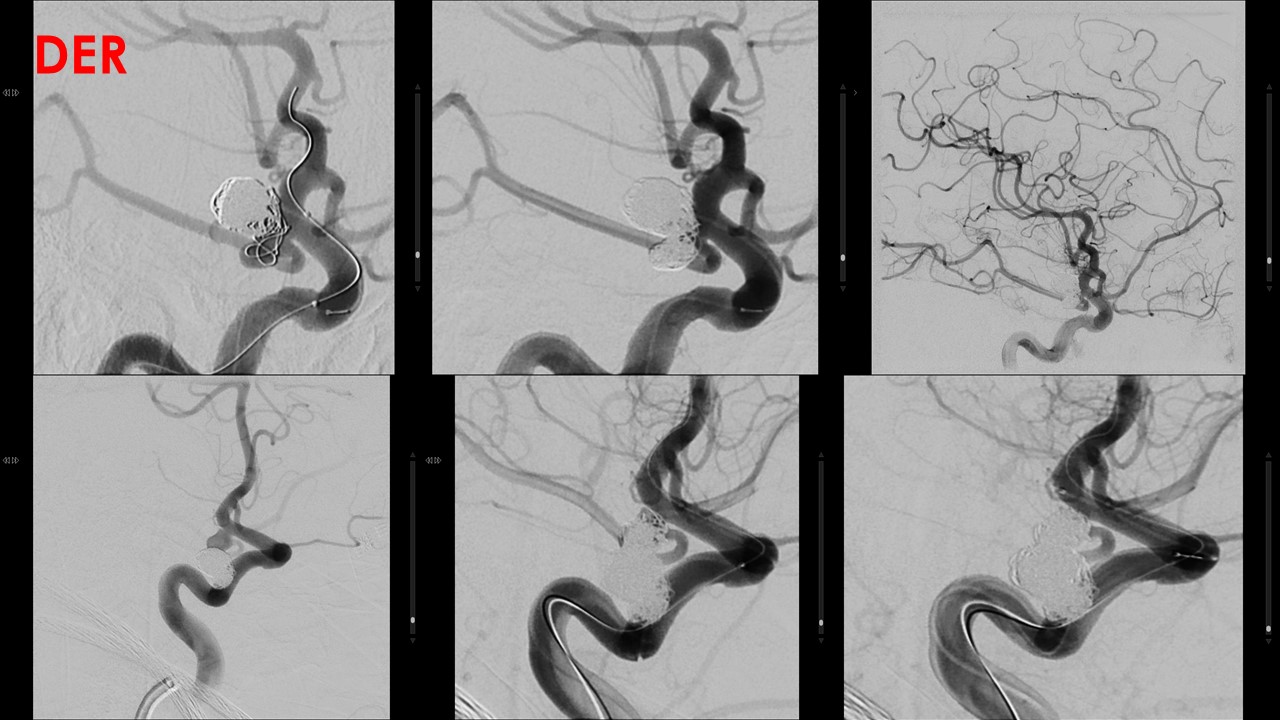

Técnica: Anestesia general. Heparinoterapia sistémica. Punción femoral bilateral.

Arterias exploradas: Arteria carótida interna derecha con proyecciones AP, Lateral, 3D y oblicuas Arteria

carótida interna izquierda con proyecciones AP, Lateral, 3D y oblicuas Arteria vertebral izquierda con

proyecciones AP, Lateral, 3D y oblicuas

Material utilizado: Neuron MAX 6Fr, Cateter Slipcat 5.5 Shuttle Simons 2 (carotida derecha), microcateter

Excelsior SL10, microguia Synchro 14, Guia Terumo.

Catéter Hinck para arteria vertebral izquierda (para control de ACP)

Balón Transform C Compliant 4x20mm

Coils utilizados:

ANEURISMA DERECHO:

1.- Target 360 SOFT 8mmx20cm.

2.- Target 360 SOFT 9mmx20cm.

3.- Target 360 SOFT 7mmx20cm.

4.- Target 360 SOFT 7mmx20cm.

5.- Target 360 STANDARD 7mmx15cm.

6.- Target 360 ULTRA 5mmx10cm.

7.- Target 360 SOFT 5mmx20cm.

8.- Target 360 STANDARD 4mmx15cm.

9.- Target 360 ULTRA 4mmx10cm.

10.- Target 360 SOFT 4mmx10cm.

11.- Target 360 SOFT 3mmx10cm.

12.- Target 360 STANDARD 3mmx6cm.

13.- Target 360 SOFT 3mmx10cm.

14.- Target 360 STANDARD 3mmx6cm.

15.- Target 360 HELICAL ULTRA 2mmx6cm.

IZQUIERDO

1.-Target 360 STANDARD 7mmx15cm.

2- Target 360 SOFT 6mmx10cm.

3- Target 360 SOFT 5mmx20cm.

4- Target 360 HELICAL NANO 2mmx4cm.

5- Target 360 NANO 2mmx4cm.

6- Target 360 HELICAL NANO 2mmx4cm.

7- Target 360 NANO 2mmx3cm.

8- Target 360 NANO 2mmx3cm.

9- Target 360 NANO 2mmx3cm.

Procedimiento: Se realiza estudio diagnóstico confirmando la presencia de dos aneurismas localizado en

origen de comunicantes posteriores:

El derecho de 11x9x8mm con cuello de 5.3mm de morfología polilobulada, en su componente inferior se

origina la comunicante posterior.

El izquierdo de 6.6×4.5×6 con cuello de 3.12, comprometiendo el origen de comunicante posterior.

Se realiza microcateterismo selectivo del saco aneurismático derecho, con protección de balón Transform,

el cual se ubica en carótida previo a la bifurcación, posteriormente se dispone en su interior un total de 15

coils. En la serie angiográfica de comprobación se identifica persistencia de mínimo saco residual con

permeabilidad de la comunicante.

En un segundo tiempo se realiza microcateterismo selectivo del saco aneurismático izquierdo, con

protección de balón Transform, el cual se ubica en carótida previo a la bifurcación, posteriormente se

dispone en su interior un total de 9 coils. En la serie angiográfica de comprobación se identifica

persistencia de mínimo saco residual y ausencia de permeabilidad de comunicante posterior, pero con

adecuada permeabilidad de ACPI desde basilar.

No se detectan incidencias durante ni inmediatamente tras el procedimiento.